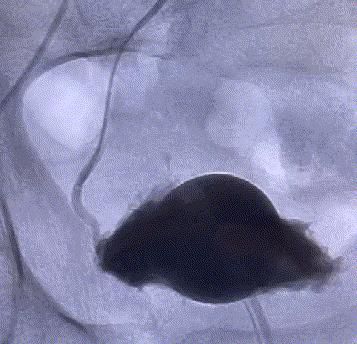

随後,李旭丹主任攜手胡志華主任爲患者實施介入治療,采用改良Seldinger法穿刺股動脈,在DSA引導下經動脈自然腔道,将微導管分别送達雙側髂内動脈進行造影,觀察雙側前列腺動脈分布情況,将微導管超選擇至雙側前列腺動脈,準确置入PVA栓塞材料,成功阻斷前列腺的營養供給,順利完成了治療。

△術前,可見前列腺供血豐富。